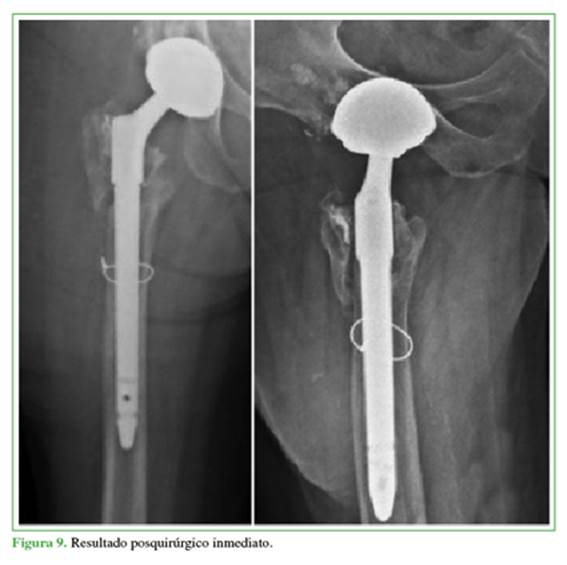

En cuanto a los resultados, se logró la resolución de la inestabilidad protésica, sin nuevos episodios de luxación hasta la fecha. La paciente reinició su rehabilitación con deambulación desde las 48 horas posteriores a la cirugía utilizando dos bastones canadienses por 3 semanas, luego deambuló con un solo bastón por otras 3 semanas, hasta lograr la deambulación independiente. Se realizó la revisión del implante a fin de corroborar la preservación del stock óseo y el correcto balance de las partes blandas y la longitud en el miembro afectado (Figura 9). Se llevó a cabo un seguimiento de 24 meses y se evaluó la evolución mediante el score de Harris modificado: el puntaje estimado era de 4/80 (mal resultado) en el preoperatorio, y este pasó a 61/80, 73/80 y 76/80 a los 3, 6 y 9 meses de la cirugía, respectivamente, lo que se considera un excelente resultado. Con respecto al nivel de deambulación, el resultado funcional mostró grandes cambios entre las evaluaciones pre- y posoperatorias. En concreto, la paciente deambula sin necesidad de aditamentos ortopédicos y sin dolor, no existe discrepancia de miembros y no presentó nuevos episodios de luxación.

En el análisis radiológico posquirúrgico de la placa, se evidenció un incremento del offset horizontal, que pasó de 39 mm a 42 mm por el uso del offset extendido. Esto se determinó por el método por Bellova y cols.,16 en el cual se traza una línea que une los centros de rotación independientes de la copa no cementada y la copa DM. Al tener una orientación independiente, la copa DM presenta una inclinación de 41,3°, diferente de la copa no cementada (42,7°), lo que optimiza la inclinación y la anteversión. Se mejoró la discrepancia de miembros hasta lograr una diferencia de solo 1 mm (Figura 10). En la evaluación radiográfica a los 24 meses del procedimiento, se evidenció la consolidación completa del fémur proximal y no se encontraron cambios en los valores de inclinación, anteversión y offset, ni signos de aflojamiento en la interfaz entre la copa no cementada y la copa DM. Del mismo modo, no se observaron signos de aflojamiento en ninguno de los componentes (Figura 11).